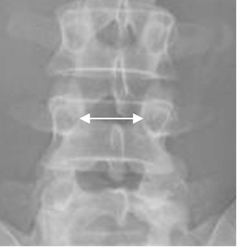

Fig 61. Distancia interpedicular.

Rx AP lumbar. Distancia interpedicular normal.